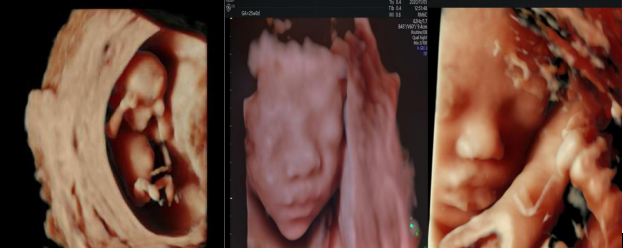

得益于煊光成像技术,胎儿在子宫中的样子非常清晰

煊影成像技术:使三维图像更加逼真(早、中、晚孕期)

四维超声模式下输出功率指数与二维超声模式下相同,对胎儿无任何伤害